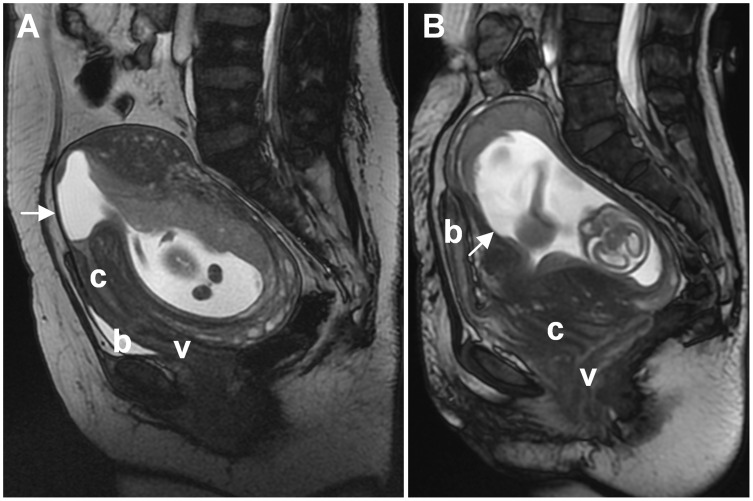

Incarceration of the gravid uterus (IGU) is a rare and serious condition associated with significant maternal and fetal morbidities. Its occurrence in women with a history of cesarean section (CS) poses a great challenge to obstetricians. We report two cases: Case 1 presented with acute urinary retention at 11 weeks of gestation, with IGU diagnosis ultimately established at 15 weeks following persistent symptoms. Initial manual reduction attempts failed, but resolution occurred later. Case 2 developed severe urinary retention at 16 weeks, and the uterus was repositioned after Foley catheter placement. Both patients underwent uncomplicated cesarean deliveries at term. To delineate the clinical characteristics and optimal management of this condition, we conducted a comprehensive literature review and identified 29 additional cases reported over the past 40 years. Analysis revealed a median gestational age of 17 weeks at presentation and 37 weeks at delivery or pregnancy termination. Among them, 16 had one or more risk factors in addition to previous CS. Clinical presentation and treatment methods paralleled those described in non-CS patients. Successful resolution with favorable outcomes was achieved in 19 cases, with interventions initiated before 20 weeks demonstrating a higher resolution rate. Severe maternal complications occurred in 30% of cases, predominantly in unresolved ones, including two uterine ruptures. Early diagnosis and active management are crucial for optimizing obstetric outcomes and reducing maternal complications in these patients.